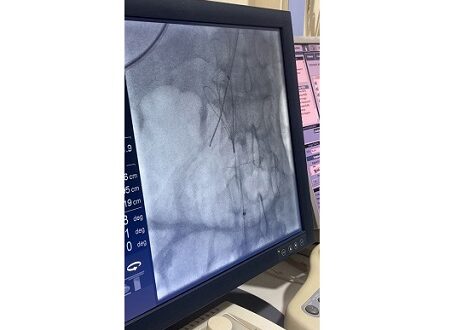

إبداع طبي: TIPS معكوس لتجاوز انسداد تام

وبسبب الانسداد الكامل في المسار التقليدي، تم تنفيذ TIPS بطريقة معكوسة (Inverted TIPS)، حيث أُدخلت الدعامة عبر الجلد، مروراً بالكبد، لتصل إلى فرع من الوريد البابي، ثم عَبَرت الكبد مجدداً إلى الوريد الأجوف السفلي تحت مستوى الانسداد. وقد أدى هذا الابتكار إلى استعادة تدفق الدم وتخفيف الضغط البابي، مما أنهى النزيف والاستسقاء وساهم في استقرار حالة المريض بشكل كبير.